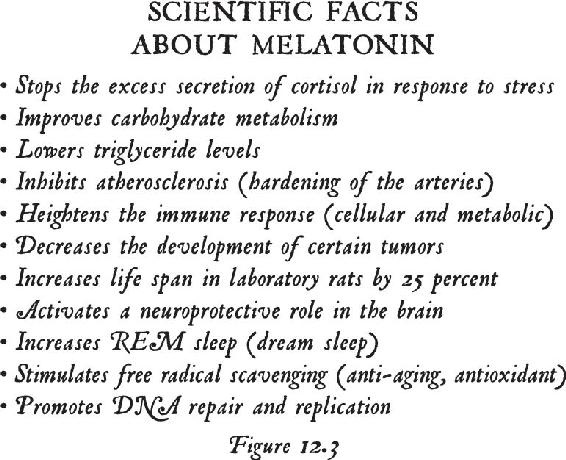

Once you are beyond your associations to this material world and you are in the unified field—chock-full of infinite possibilities—biological systems exist for taking that energy that’s beyond the vibration of matter and turning it into imagery in the brain. That’s where the pineal gland comes in, the subject of Chapter 12. Think of your pineal gland—a tiny gland perched in the central back area of your brain—as an antenna that can transduce frequencies and information and turn them into vivid imagery. When you activate your pineal gland, you are going to have a full-on sensory experience without your senses. That internal event will be more real to you in your mind while your eyes were closed than any past external experience you’ve ever had. In other words, in order to lose yourself fully in the inward experience, it has to be so real that you are there. When this happens, this little gland transmutes melatonin into some very powerful metabolites that cause you to have that type of experience. We will study the properties of this gland and then you will learn how to activate it.